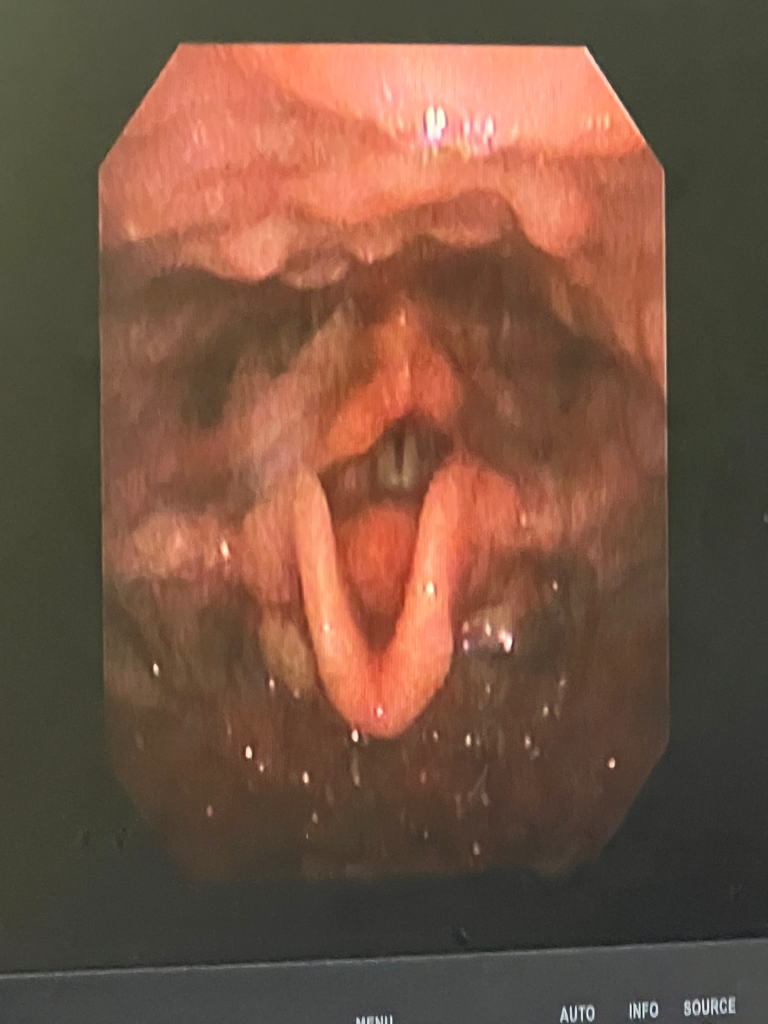

역류성 식도염으로 인한 증상의 가능성이 생각됩니다,

약물치료와 함께 증상의 개선 여부를 확인해보시고 증상을 악화시킬 수 있는 좋지못한 식습관을 고치고, 금주, 금연, 카페인 섭취를 피하시기 바랍니다,